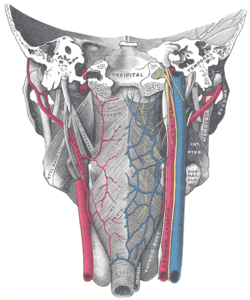

Muscles of the pharynx, viewed from behind, together with the associated vessels and nerves. (Pharyngeal plexus visible but not labeled.) | |